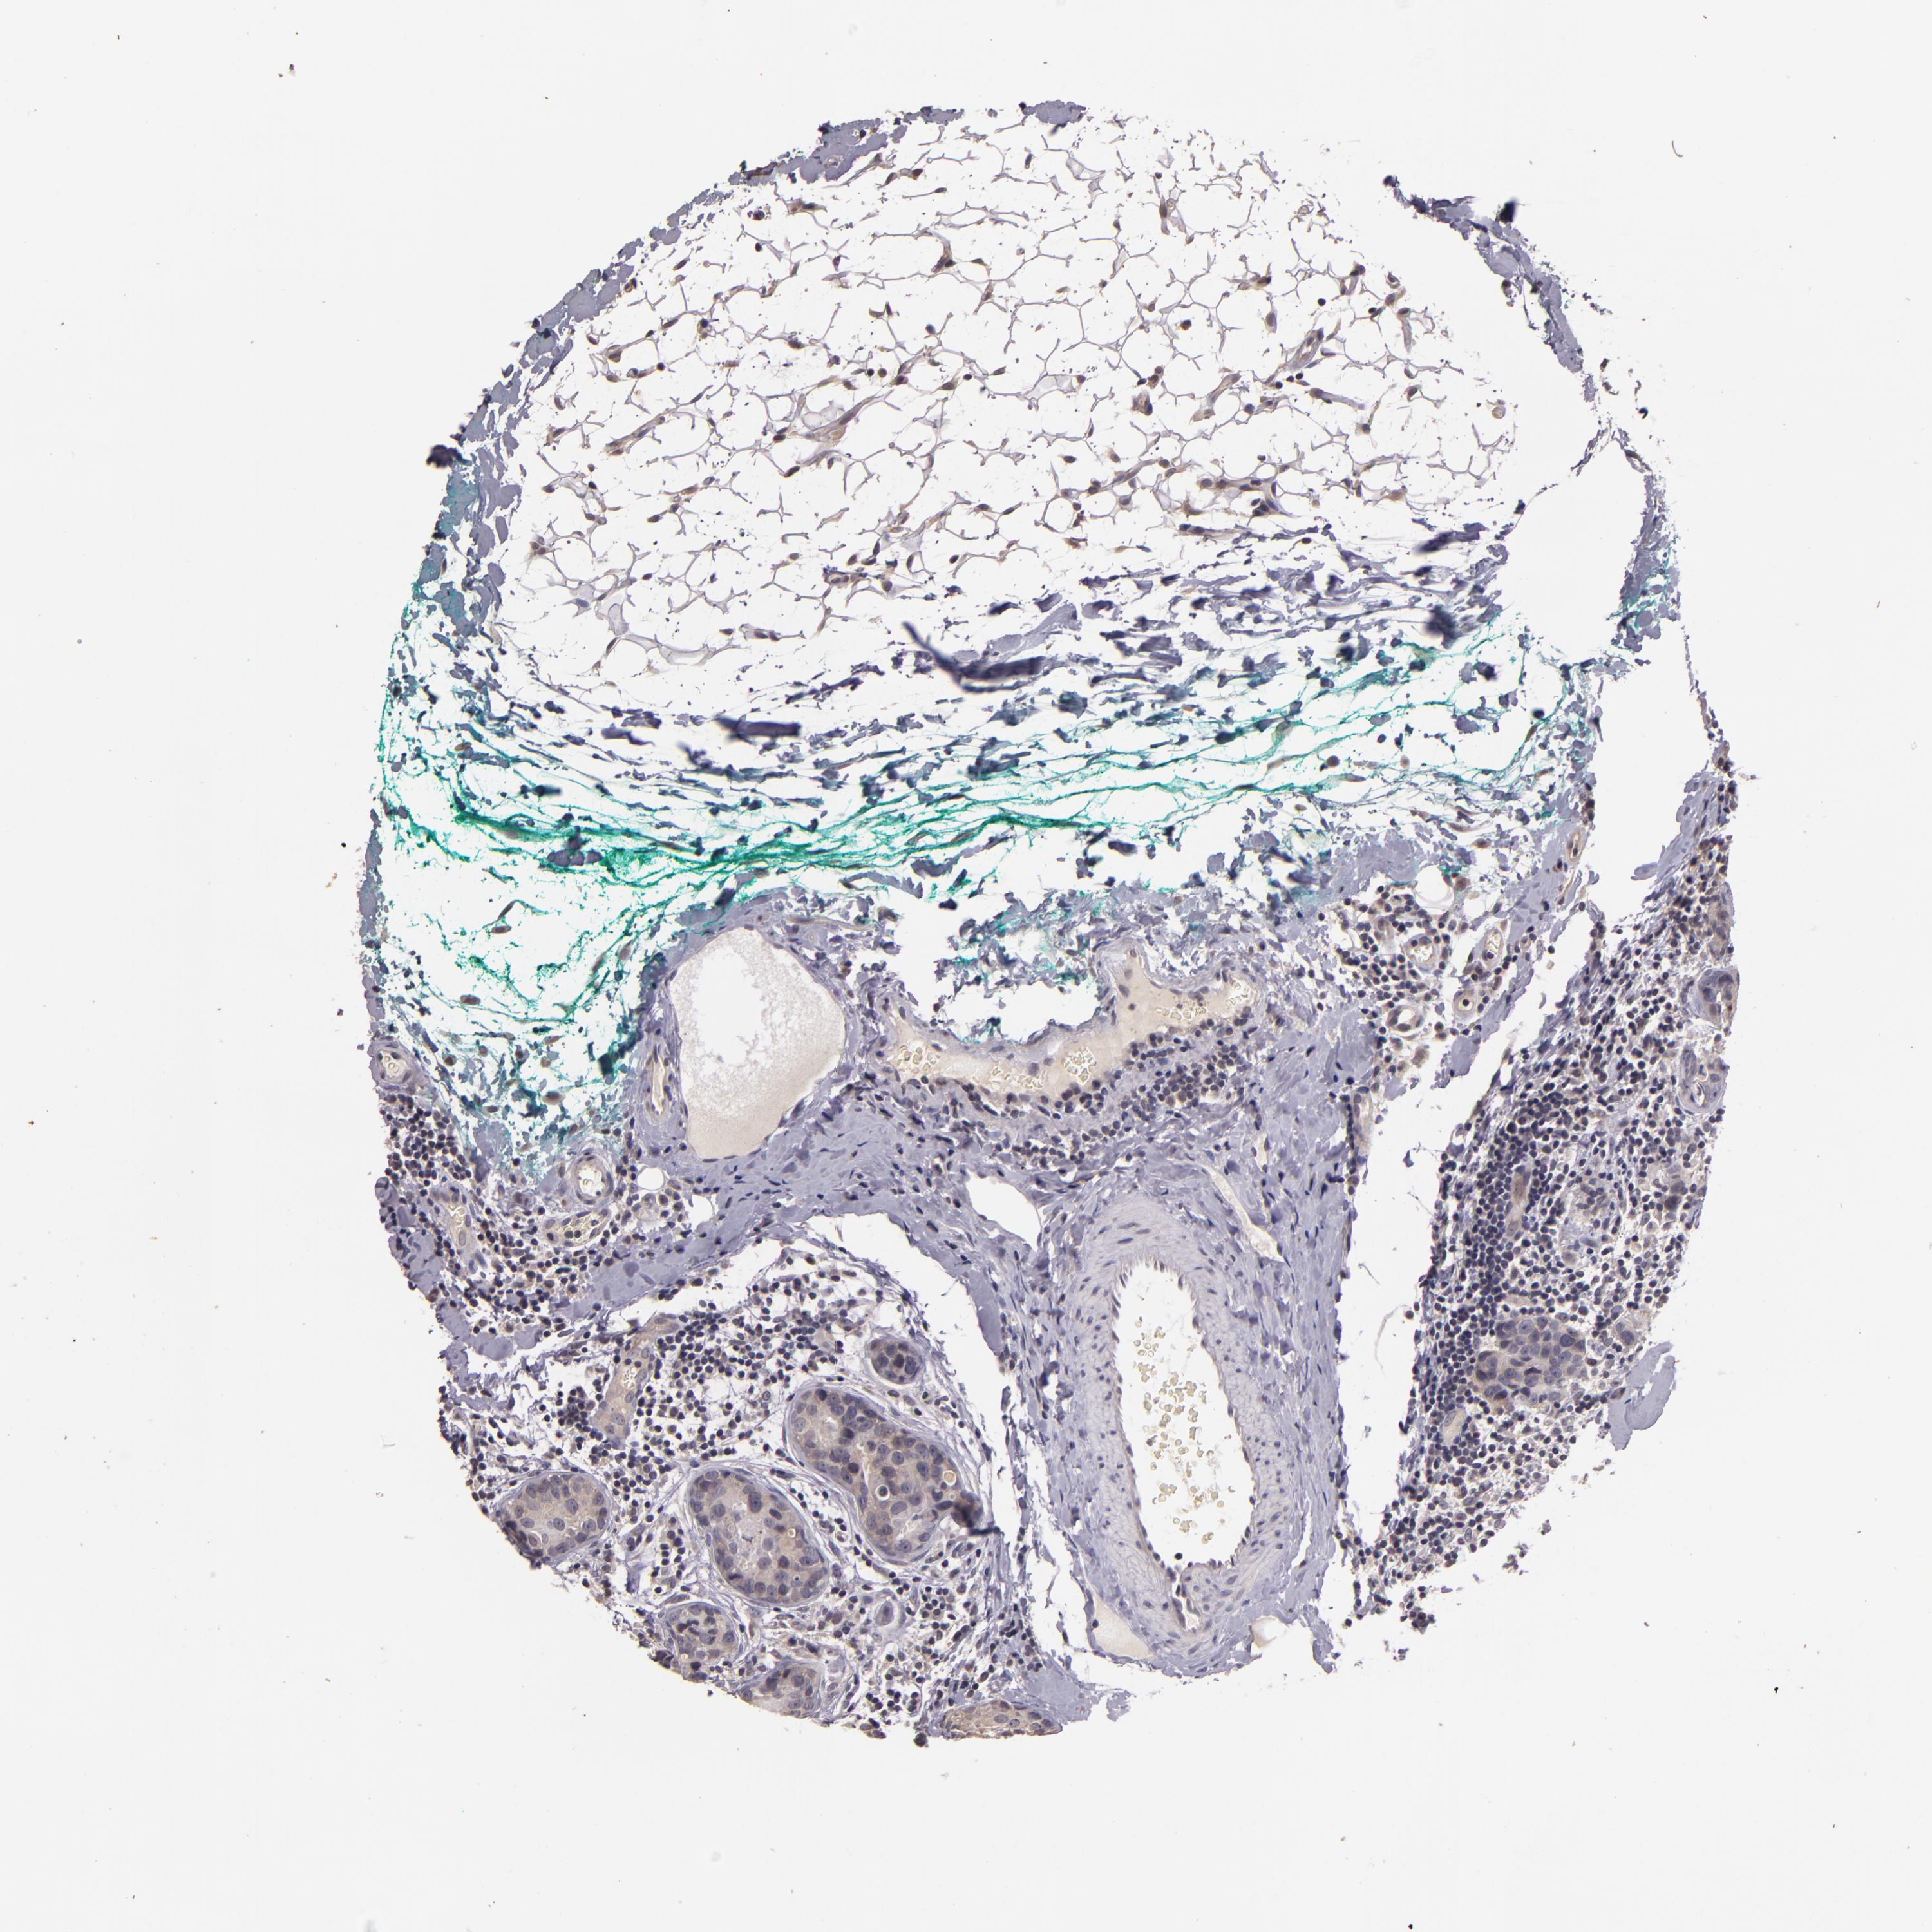

CANCER BREAST CANCER Show tissue menu

Breast cancer

Human cancer